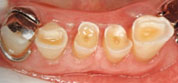

- WSD

- アブフクラクション・楔状欠損(WSD)